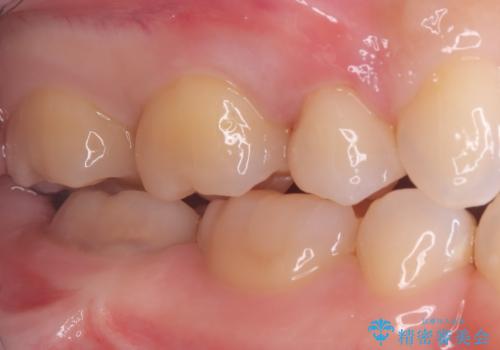

後日、歯の色調に合わせてオーダーメイドで作製されたセラミックインレーを装着。セラミックは天然歯のような透明感があるため、修復した箇所がどこかわからないほど自然な仕上がりとなりました。

また、セラミックは汚れ(プラーク)が付きにくく、経年劣化による変色もほとんどないため、再発リスクを抑えつつ、長期的に白く美しい状態を維持することが可能です。機能・審美の両面で、患者様にご満足いただける結果となりました。